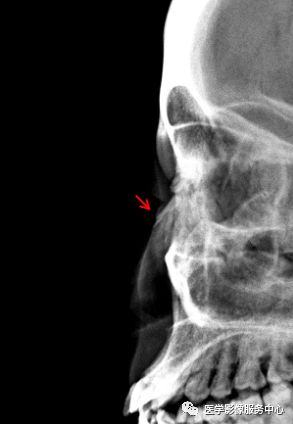

鼻骨

两个病例均显示:鼻骨中远段骨质连续中断,断端向内下方移位。鼻骨骨折。Warmreminder:鼻部受伤,有时鼻骨骨折不能做出诊断。小妙招鼻骨双侧位更容易观察。